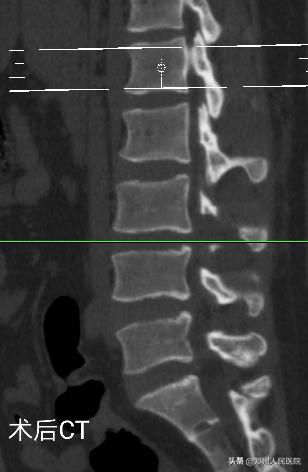

经过充分准备,对小葛实施的“单侧双通道UBE脊柱内镜术”如期举行。手术进行的十分顺利,经过一个半小时,手术成功。

在度过神经水肿期后,小葛的疼痛便消失了大半,由于手术对骨质的破坏很小,脊柱的稳定性得以最大程度的保留,手术后3天小葛就可以在腰部支具的辅助固定下行走活动,往日开朗的笑容又重新回到他的脸上。

为刘叔进行的“单侧双通道UBE脊柱内镜术”在不足两个小时后顺利结束,术中麻醉效果极佳,出血量只有数十毫升,清晰放大的视野下,突出的髓核及增厚的黄韧带完全摘除,骨性狭窄磨钻安全扩大减压,偶尔出现的小出血点也在射频刀头的控制下立即止血,轻松漂浮的神经根又重新出现了。

手术后,田明波主任问刘叔手术前后的感受,他只说了一句话,“要知道这个微创手术效果这么好,真是该早点来手术”。